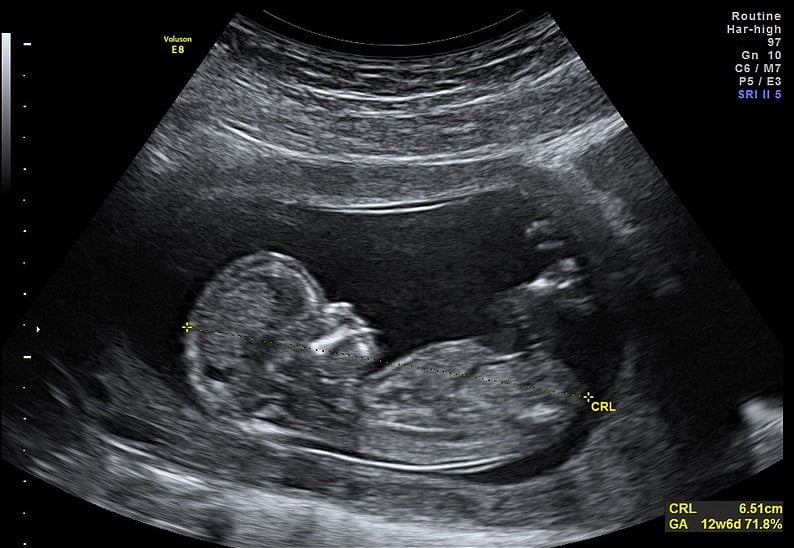

Instead, pregnancies are dated based on the crown-rump length (CRL), measured by ultrasound scan between 10+0 and 13+6. This way, we avoid unnecessary inductions for ‘post-dates’ based on LMP recalled later than in reality, and we can monitor labours where the LMP date suggests is over 37+0 but the scan suggests is preterm.

Fig 1 - Ultrasound scan of a pregnancy at 12 weeks, showing the measurement of the crown-rump length.

Ultrasound scan of a pregnancy at 12 weeks, showing the measurement of the crown-rump length.